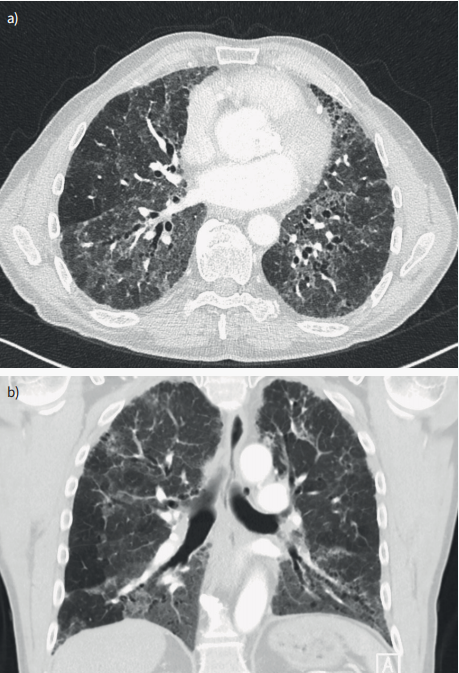

HRCT在HP的诊断和纤维化的检测中起着关键作用。HP的典型CT表现为组织病理学上以细支气管为中心的炎症导致的分布于肺各区域的小而边界不清的磨玻璃结节(图1);它也可能导致小气道狭窄,形成小叶空气潴留。更广泛的肺间质炎症可导致磨玻璃影和肺密度增加。在HP中,这种磨玻璃影通常呈斑片状分布,称为马赛克衰减(图1和图2)。磨玻璃影、血管纹理减少的低密度影和正常肺组织3种不同密度影像同时存在被称为三密度征(曾称猪头乳酪征、肉皮冻征等),这是HP特异性的CT表现。纤维化的表现包括小的蜂窝状结构和粗糙的网状结构或磨玻璃影与牵拉性

图1 HP的HRCT。a.吸入抗原引起的以细支气管为中心的炎症,CT示边界不清的小叶中心磨玻璃结节;b.呼气扫描时的空气潴留;c.弥漫性间质炎症导致磨玻璃和肺密度增加,可见血管和支气管壁;d.马赛克衰减;e.HP特异性CT表现:三密度征。

图2 一位64岁男性纤维化HP患者的HRCT。a.轴位CT扫描;B.冠状位CT扫描;吸气时马赛克衰减,同时出现纤维化(牵拉性支气管扩张)的迹象。